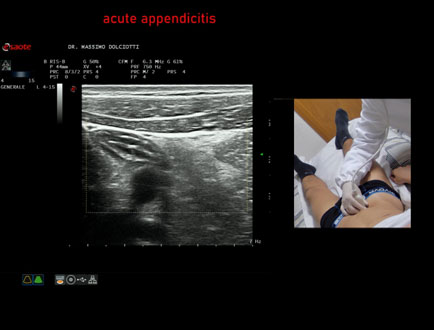

Data inserimento: 15/01/2026

Ecografia del: 07/01/2025

Strumento: Esaote MyLab Eight

Sonda: Lineare Multifrequenza 3-13 MHz

Età Paziente: F 39 anni

Motivazione dell'esame: dolori addominali epiastrici da 2 gg, anche notturni, non nausea, non vomito, non diarrea, non febbre, diuresi normale, nicturia saltuariamente.

Commento all'esame: le immagini ed il video documentano, in sede ileo-cecale, appendice di spessore aumentato (11 mm - V.N. inferiore a 6 mm). Gli elementi ecografici segnalati orientano per appendicite acuta.

Conclusioni: appendicite acuta (acute appendicitis).

In collaborazione: Dr.ssa Marica Manfredi - Ancona, Dr. Ilir Qose - Ancona

Presentazione: Dr. Massimo Dolciotti - Ancona